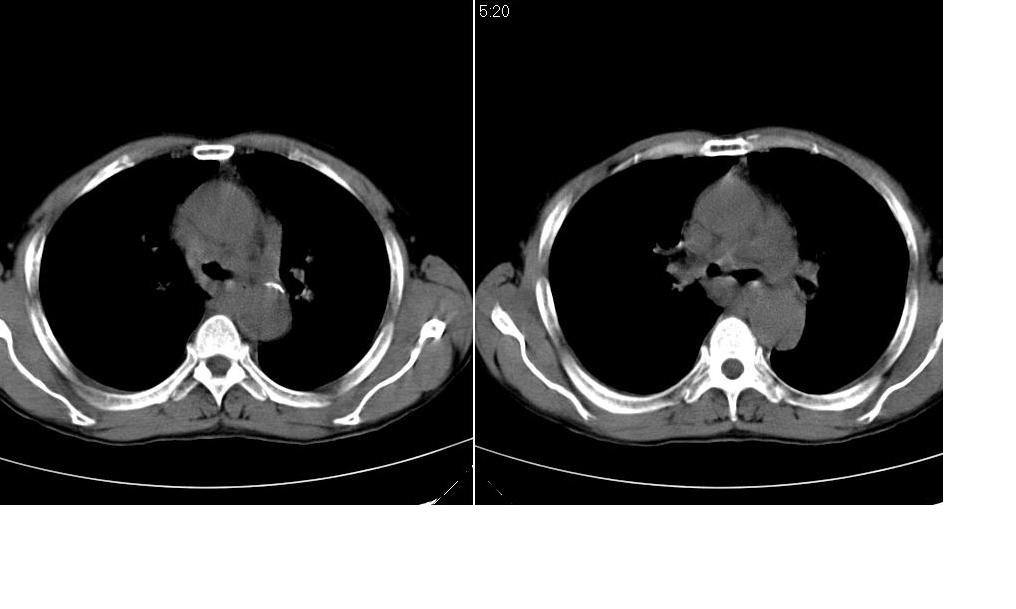

标题: CT10843:男 61岁,胸部CT平扫 [打印本页]

标题: CT10843:男 61岁,胸部CT平扫

男 61岁,已确诊肺癌半年余.

考虑:1、右肺下叶中心型肺癌并纵隔淋巴结转移。胸腔积液。

2、心包少量积液。

3、左肺改变不除外癌性淋巴管炎或化疗后肺间质纤维化。

补充一下:右肺底好象有一个类圆形的结节影,可考虑为肺部转移。如图示。[

考虑:1、右肺下叶中心型肺癌并纵隔及左肺门淋巴结转移。胸腔积液。

3、左肺改变与左肺门肿大淋巴结影压迫主支气管有关。